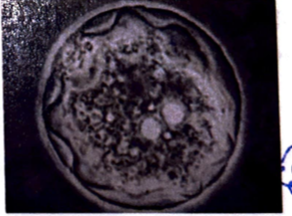

Entamoeba coli cyst